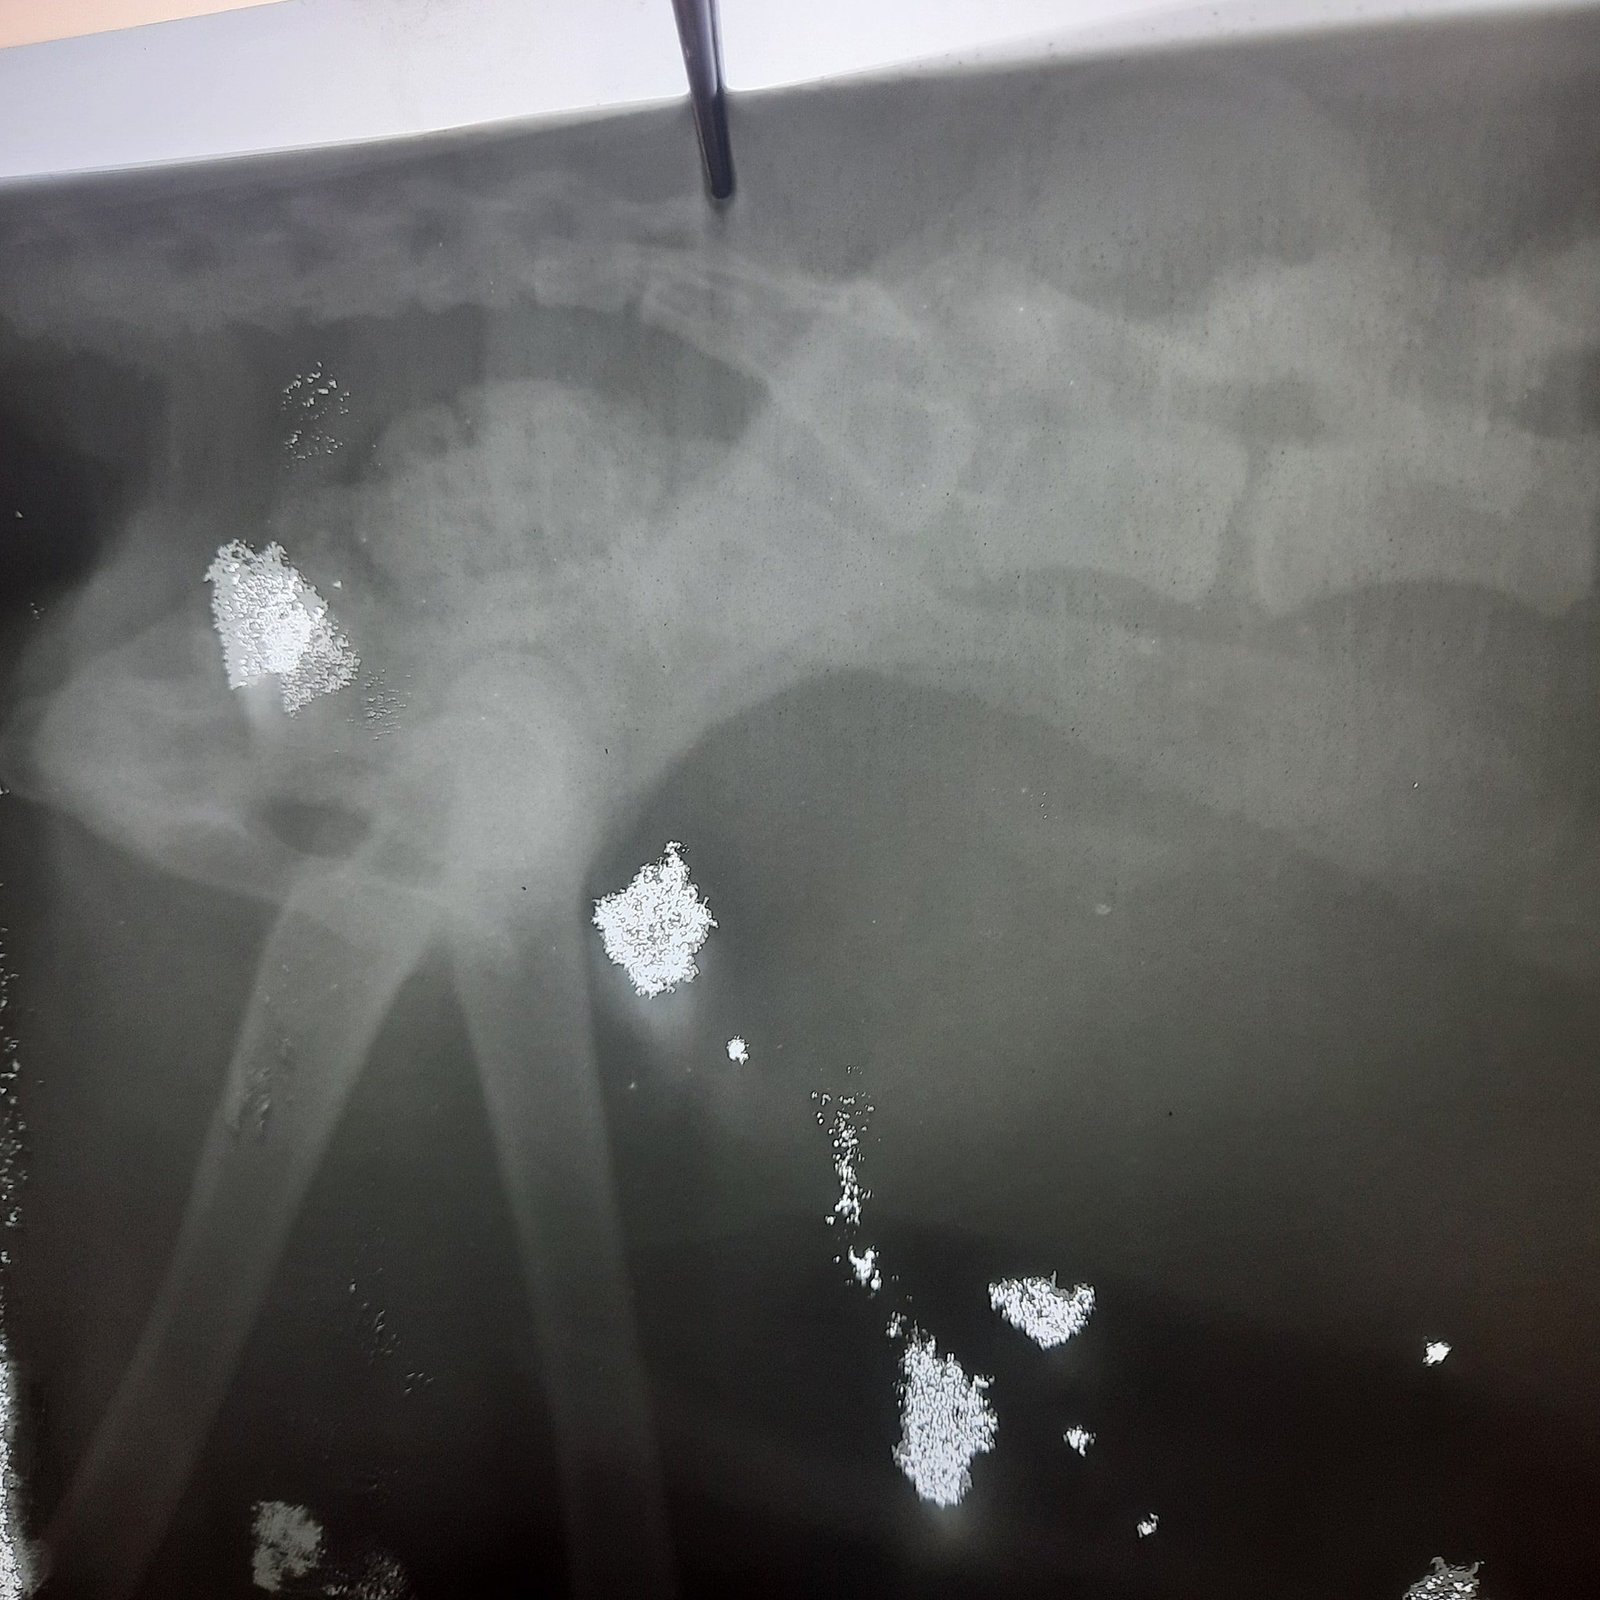

He's quite an old male and his X-rays show he has a spinal fracture similar to the one that Tinkerbelle had so we hoped a course of laser therapy would heal it.